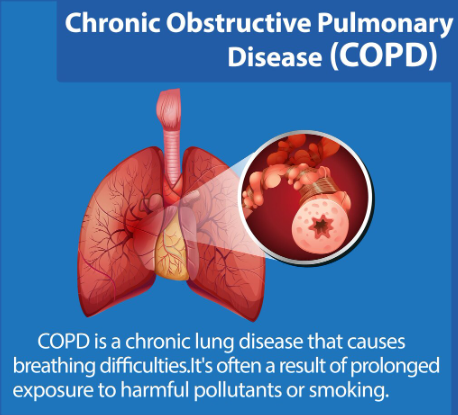

- Chronic Obstructive Pulmonary Disease (COPD): Progressive lung conditions including emphysema and chronic bronchitis

COPD Management: As the best hospital for COPD treatment Hyderabad, Revive Hospitals offers pulmonary rehabilitation, bronchodilator therapy, oxygen support, and lifestyle modification programs. Research indicates that comprehensive COPD care can improve quality of life by up to 40% (Global Initiative for Chronic Obstructive Lung Disease, 2023).

Q: How is COPD different from asthma?

A: While both affect breathing, COPD is typically progressive and caused by long-term exposure to irritants like smoking, whereas asthma is inflammatory and often reversible with proper treatment. Both require specialized pulmonology care.